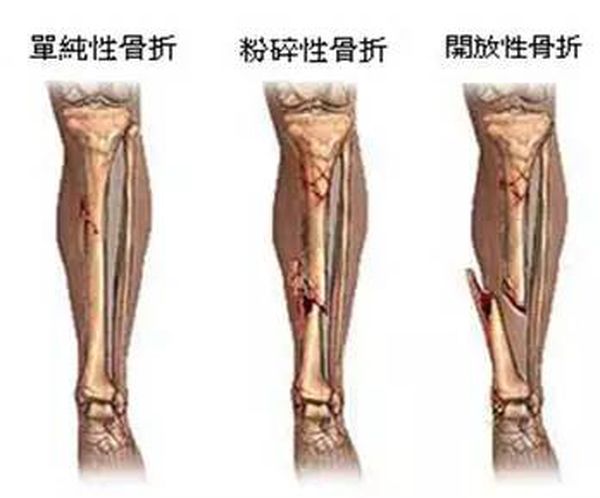

外伤骨头——粗看X线片,细看CT,核磁看不清

各种外伤,如果怀疑伤到了骨头,优先选择X光照片,检查结果快速易得。若要进一步观察,可以选择CT。超声、核磁对于骨皮髓质等看不大清,一般不选择。